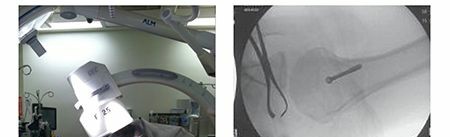

INTRAOPERATIVE PATIENT POSITIONING AND FLUOROSCOPY FOR FRACTURE SURGERY: A SUGGESTED GUIDE TO OBTAINING THE Q…